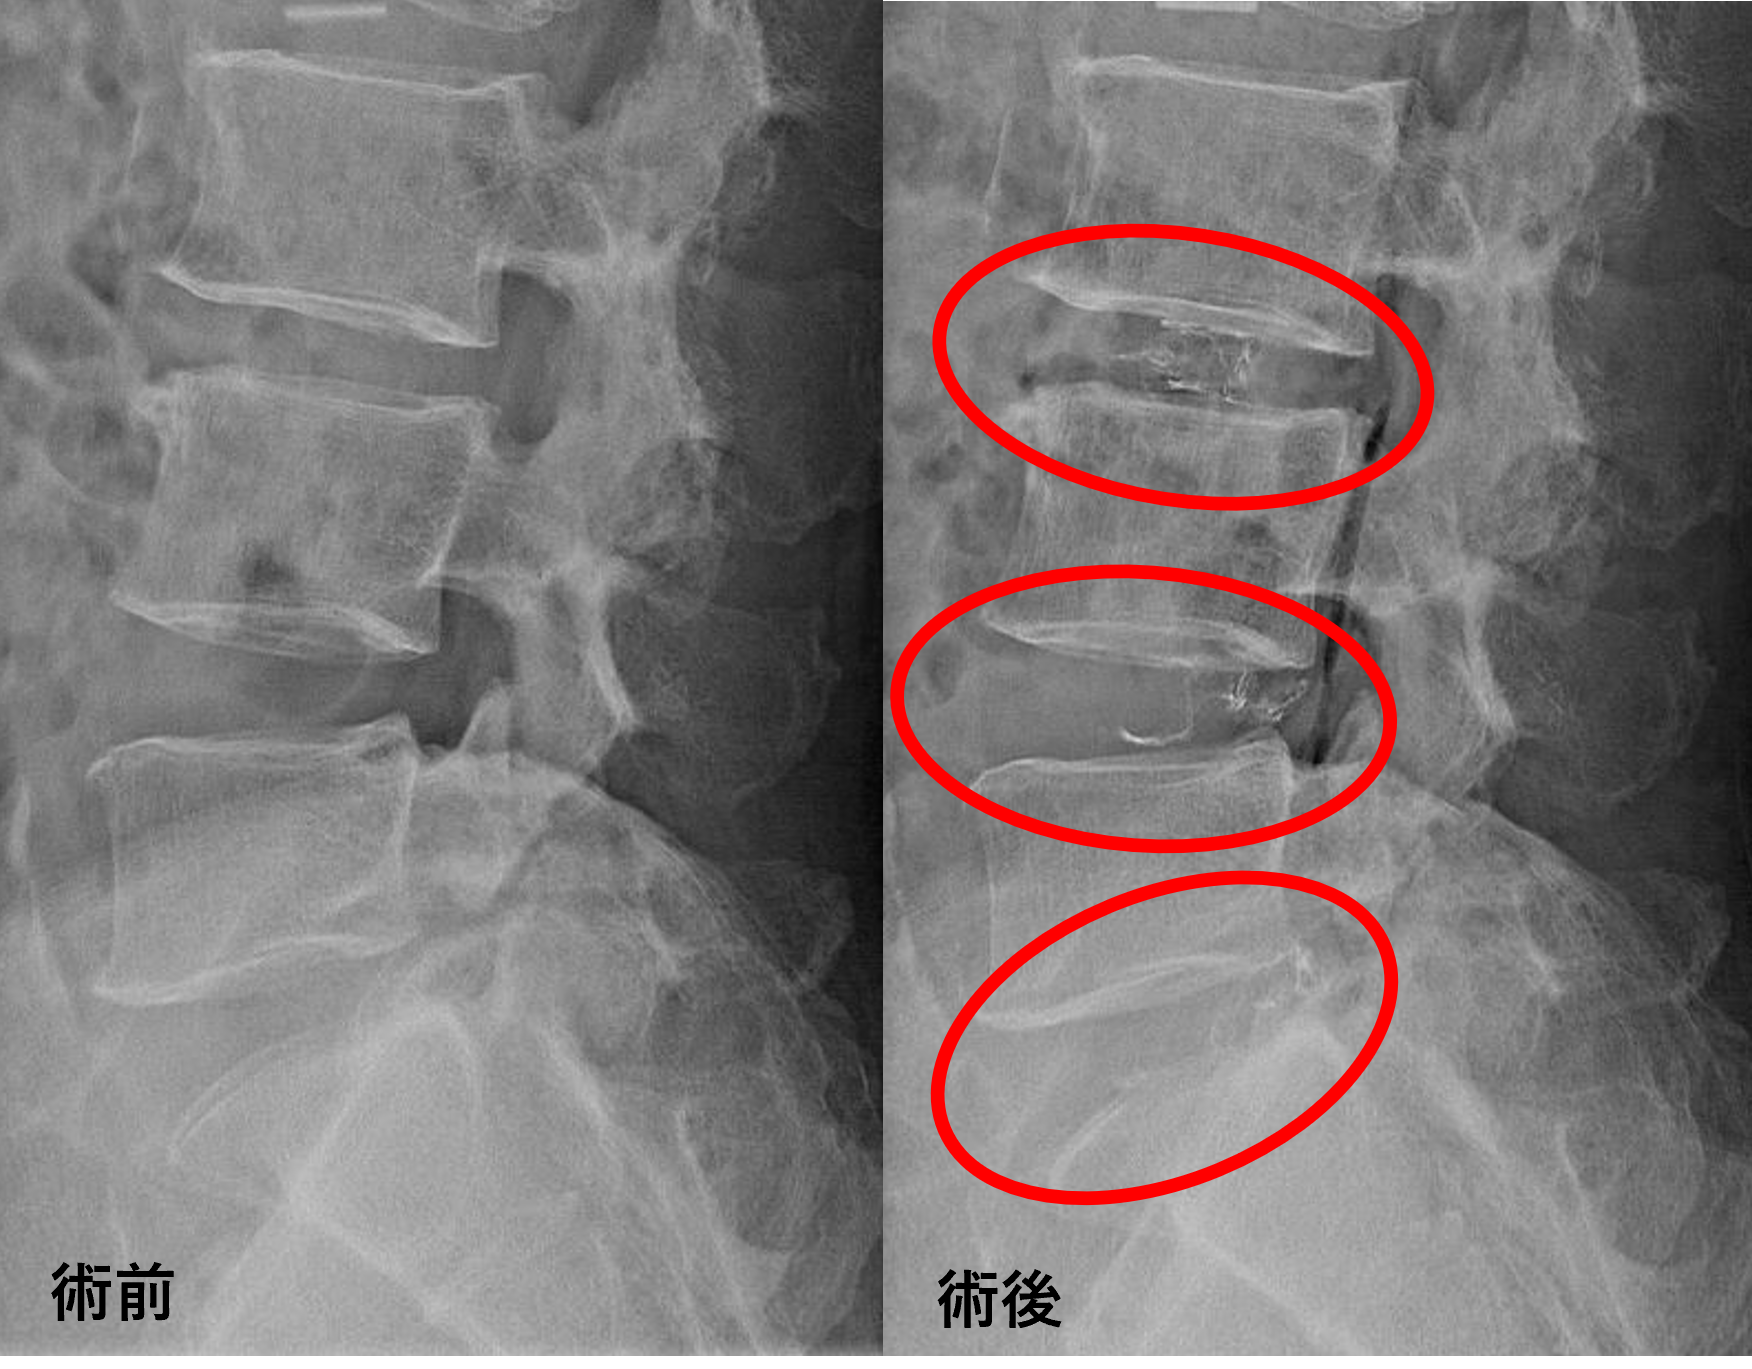

画像及び所見について

- L3/4 – 椎間板変性、膨隆、椎間孔狭窄、脊柱管狭窄

- L4/5、5/s – 椎間板変性、膨隆、椎間孔狭窄

以上のことが画像上認められました。

L3/4の椎間板所見による脊柱管の圧排が、症状の原因の可能性がもっとも高い。

L4/5、5/sの椎間板所見は、今回の症状への寄与は少なそうだが、今後は可能性がある。

患者様と相談の元、L3/4、4/5、5/sにセルゲル法を施行